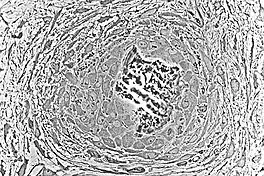

Osteoblasts (purple) rimming a bony spicule (pink - on diagonal of image). In this routinely fixed and decalcified (bone mineral removed) tissue, the osteoblasts have retracted and are separated from each other and from their underlying matrix. In living bone, the cells are linked by tight junctions and gap junctions, and integrated with underlying osteocytes and matrix H&E stain.